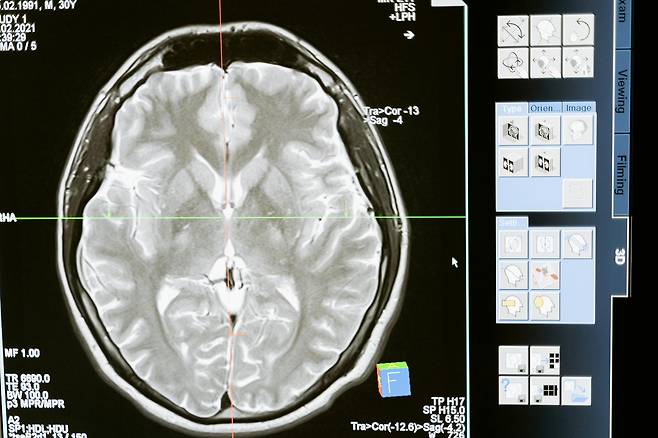

대부분의 뇌출혈 환자들이 병원에 실려오기 전 공통적으로 겪는 증상입니다. 겉으로는 멀쩡해 보이지만, 뇌 속 혈관이 터지기 직전까지 압력을 받으며 이상 신호를 보내는 겁니다.

이 증상들은 뇌혈관 내부의 압력이 급격히 올라가면서 발생하는 미세출혈 또는 혈관 파열 직전 단계의 징후입니다. 특히 고혈압을 오래 앓은 사람, 혈관 탄력이 약한 중장년층에게 더 자주 나타납니다.

뇌는 통증을 느끼는 신경세포가 거의 없기 때문에 출혈이 시작돼도 처음에는 알아차리기 어렵습니다. 출혈량이 많아져 뇌 조직을 눌러야 본격적인 증상이 나타나기 때문에, 초기 신호를 놓치면 예방의 골든타임을 잃게 되는 것입니다.